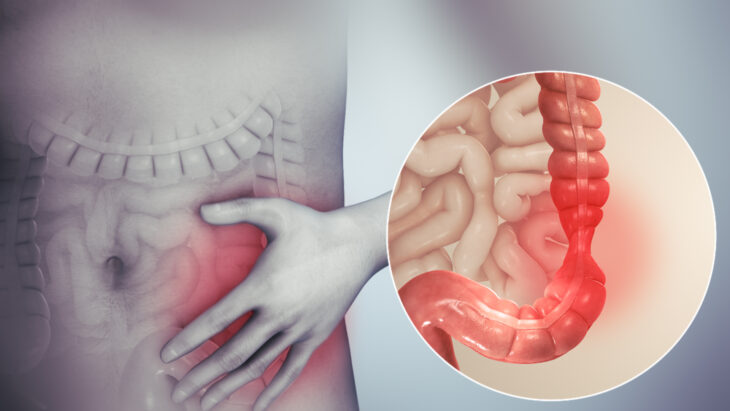

Orienta IMSS Veracruz Norte sobre prevención del Síndrome del Intestino Irritable

Xalapa, Veracruz, 5 de febrero de 2026 El Instituto Mexicano del Seguro Social (IMSS) en Veracruz Norte informa a la población en general sobre la importancia de identificar oportunamente el […]